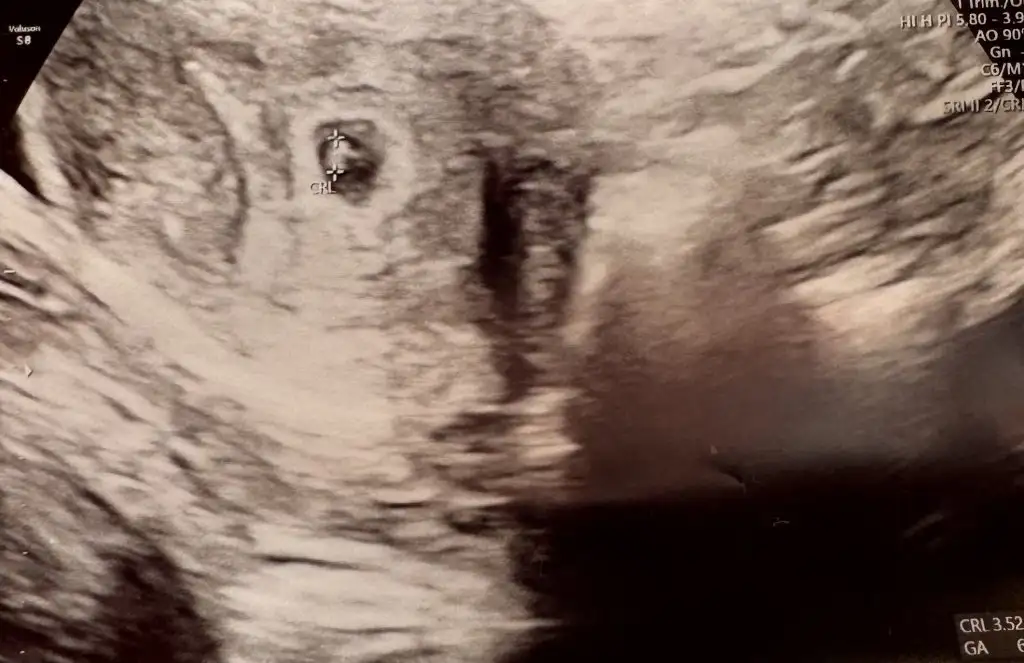

Canım bu da erkek oluyo bu teoriye göre unutmayın bunları da cinsiyet belli olduğunda karşılaştıralimKızlar kesemiz 5mm den 11mm yükselmiş 4 günde hiç bir sorun yok dedi doktor kalp atışı için erken dedi haftaya Salı yine gel dedi![]()